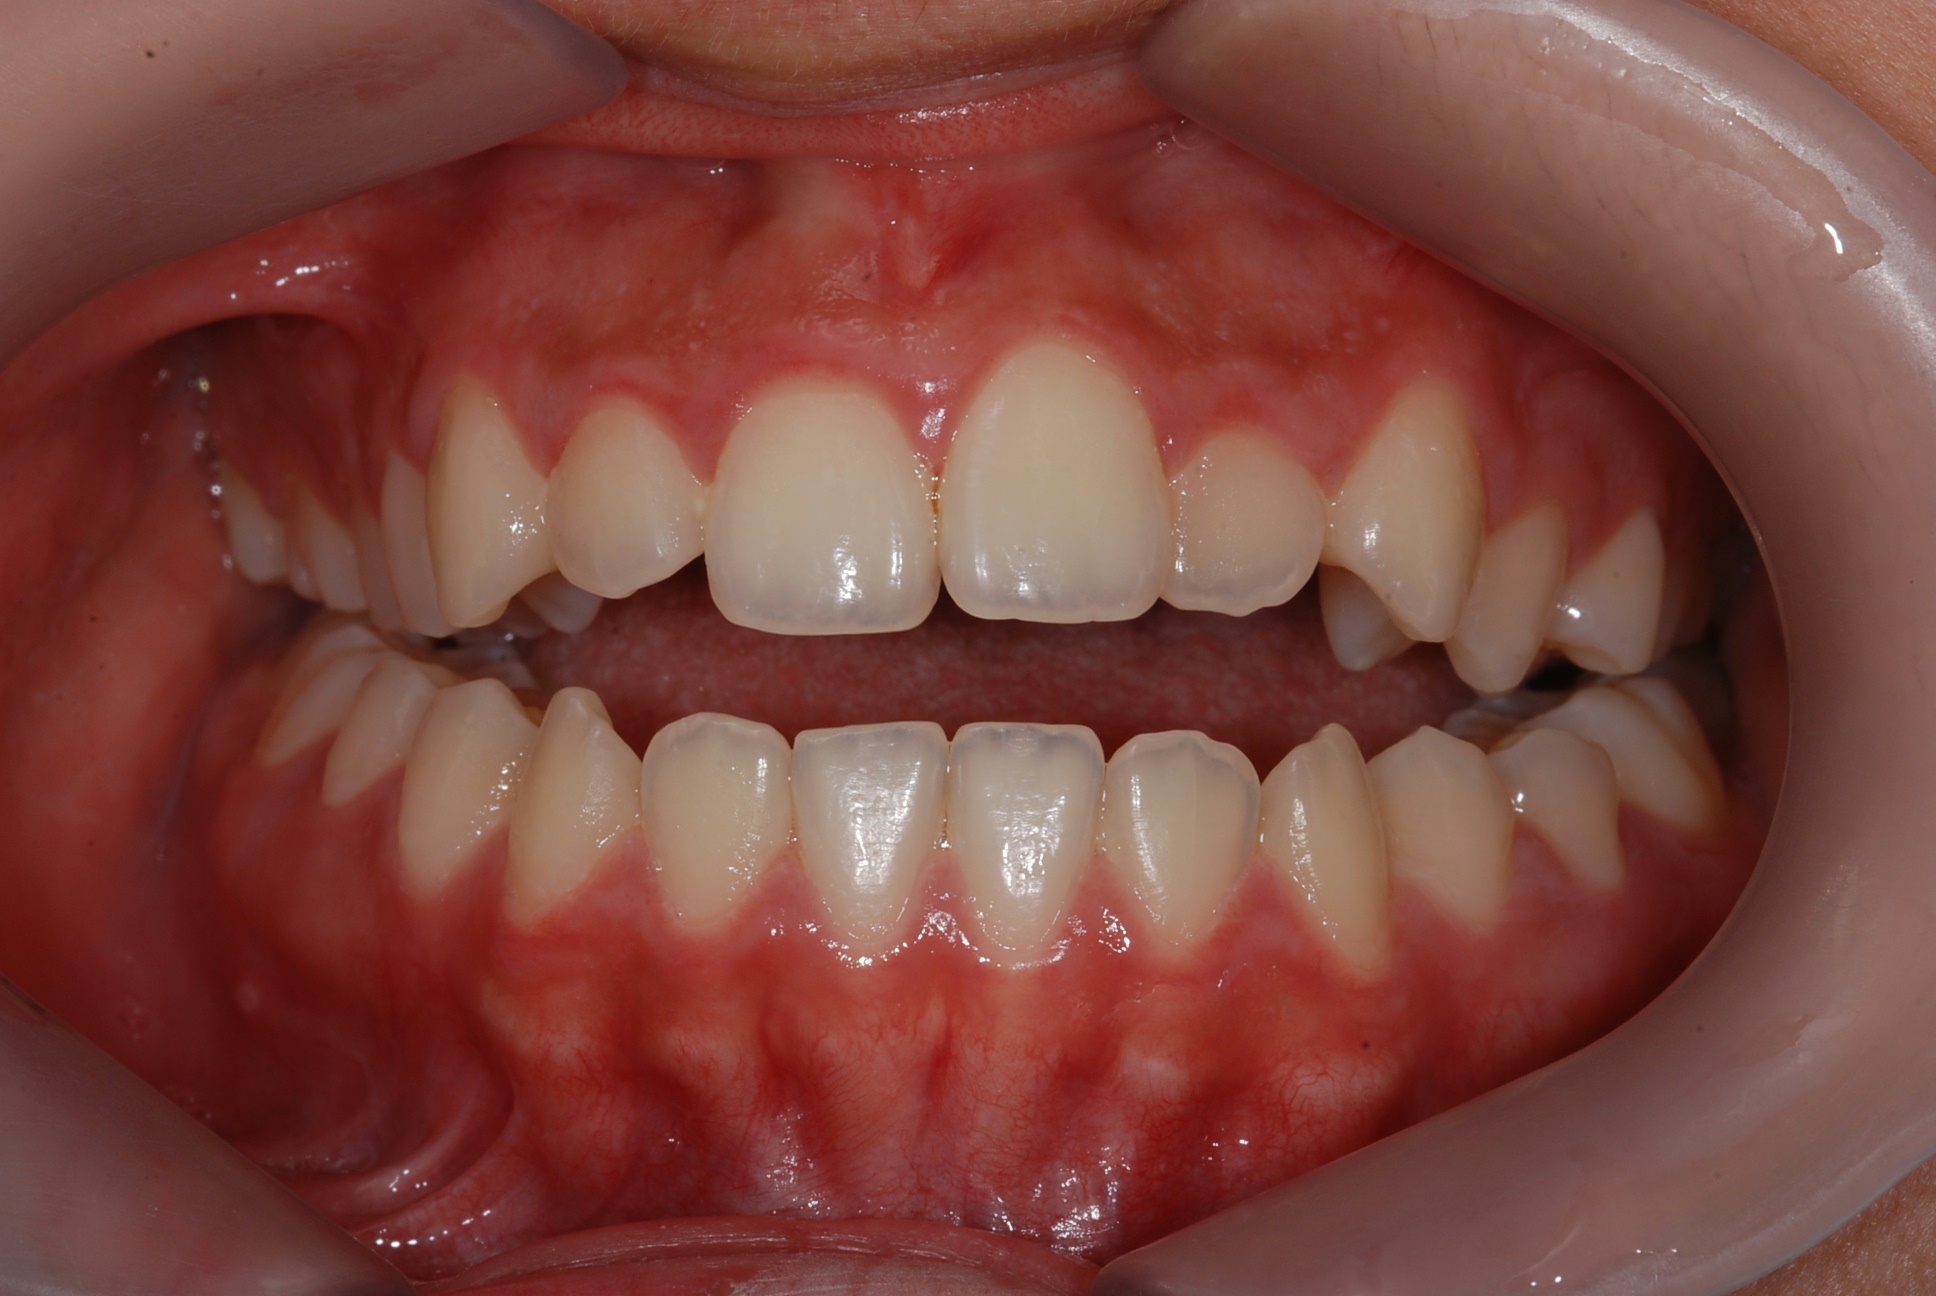

치료 후 사진입니다.